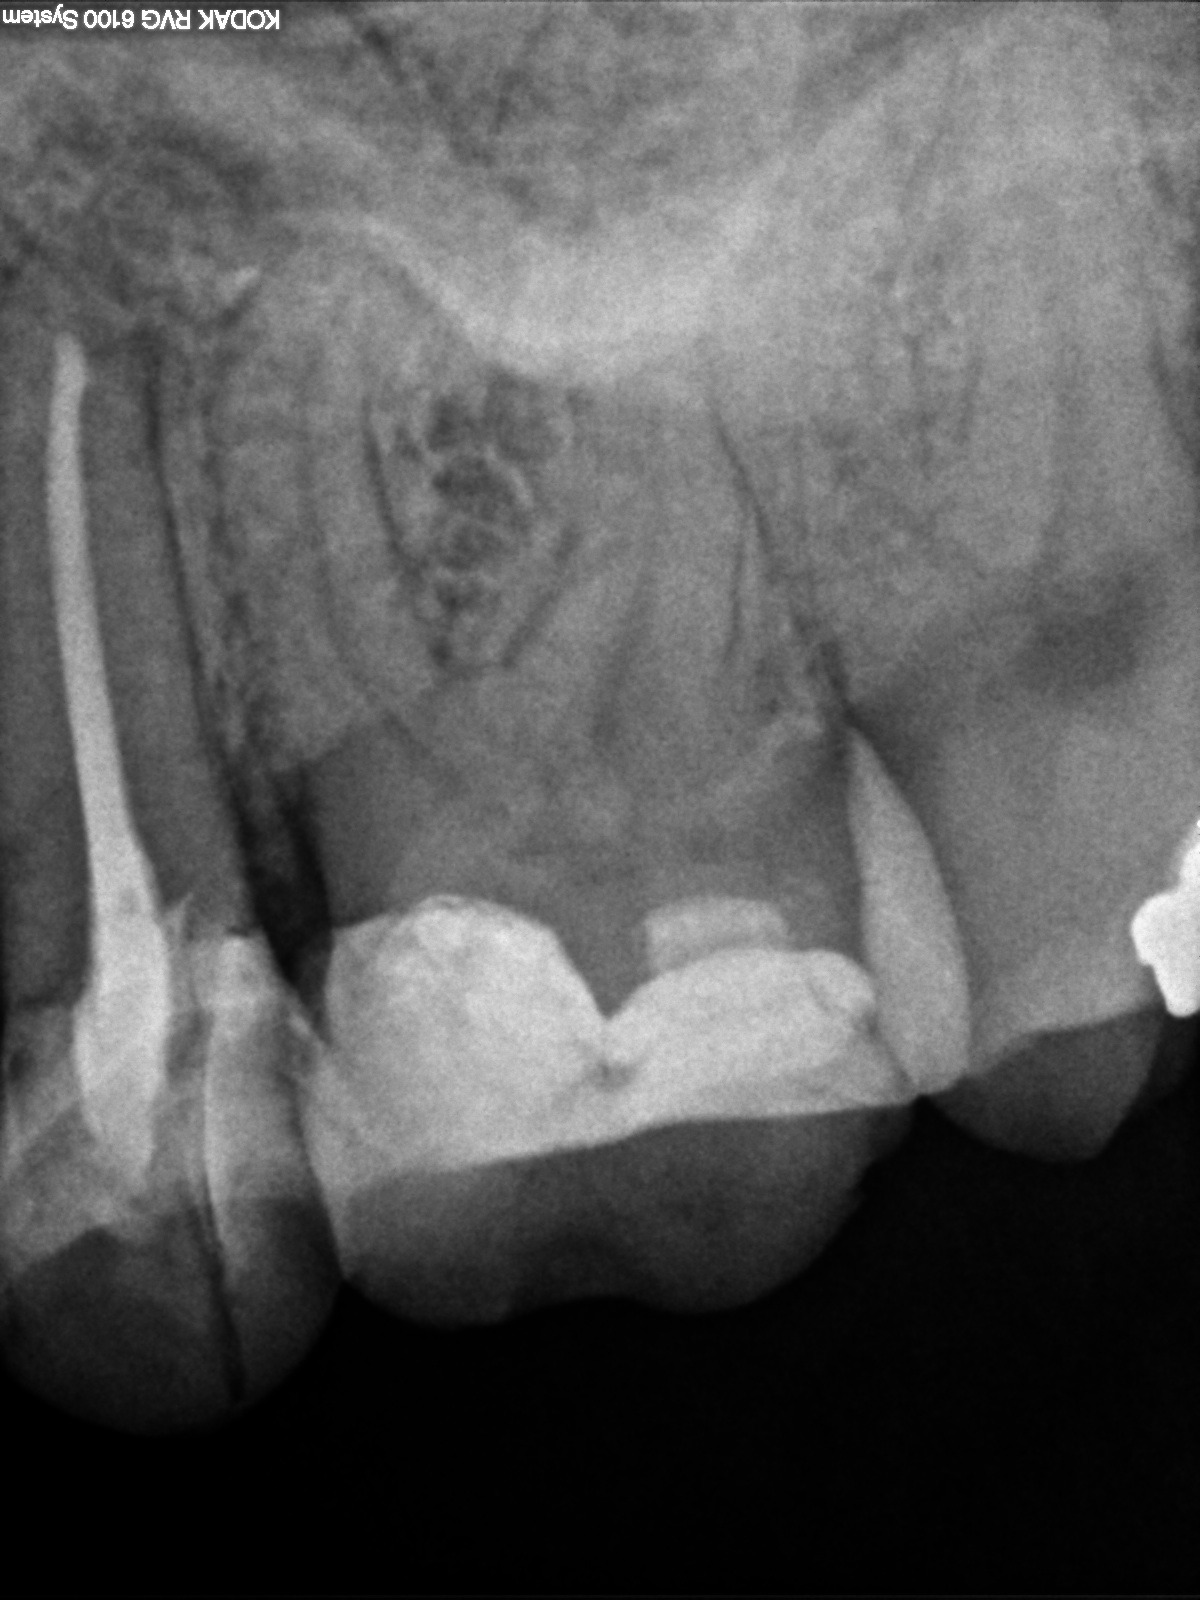

R2 Veröffentlicht 7. Oktober 2014 am 1200 × 1600 in Fragestellung: Parodontitis apicalis? Aufnahme 2013